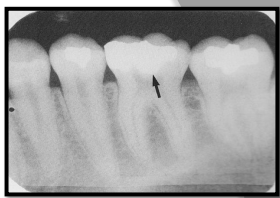

3 Criteria for a bite-wing exposuresÂ

What does #1 show?

#1 shows INCORRECT vertical angulation

it is over angulated thus obstructing the interproximal view of the lesion

#2 shows CORRECT vertical angulation

interproximal caries now visible on the radiograph.

**vertical angulation = tilting PID up or down

Correcting horizontal angulation for open contacts.

Open contacts are important for revealing interproximal caries.Â

Image 1 overlap hiding the cariesÂ

Image 2 has better horizontal angulation but still some overlap

Image 3 open contacts shows full extent of interproximal caries.Â